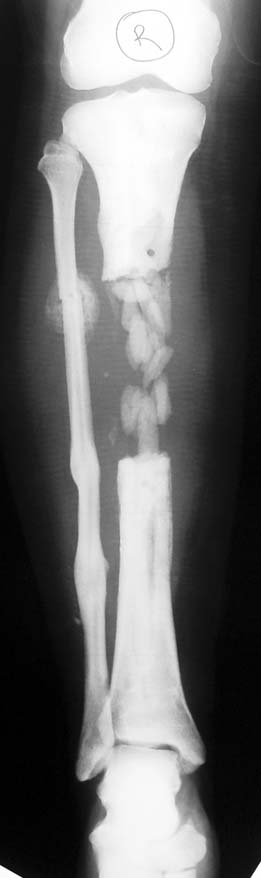

Chronic osteomyelitis leads to necrosis of bone and soft tissues. Dead bone is a nidus which hosts pathogenous microorganisms. Defence mechanisms of the host is usually not in optimum condition to deal with microorganisms. Antibiotics can’t reach the infection site because blood flow is disrupted. For these reasons, dead bone has to be completely removed by radical debridement.

Appropriate radical debridement necessitates excision of all necrotic bone and soft tissues, and frequently causes instability at the involved extremity. The remaining bone and soft tissue defect has to be fixed and reconstructed. The distraction osteogenesis method of Ilizarov is used successfully for achievement of union, correction of the deformity, elimination of limb length inequality and reconstruction of segmental bone defects.

Case 2